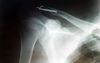

Zdar,když už se tady probírají samé drátky a šroubky tak se můžete podívat jak opravili mě. Dnes mám cca 50 dní po operaci, s rukou hejbu do všech světových stran,ale větší zátěže se zatím bojím, čekám na další rentgen a vyjádření doktorů. Na kolo si sednu jen u baráku,abych nezapoměl jak se na něj leze :-),nikam nespěchám(ale cukání mám obrovský)